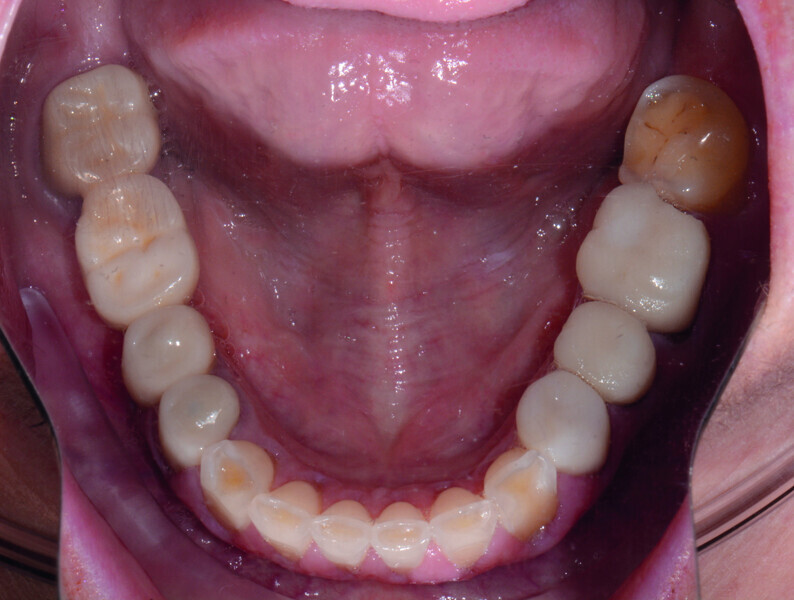

Restoring function and aesthetics with monolithic zirconia restorations